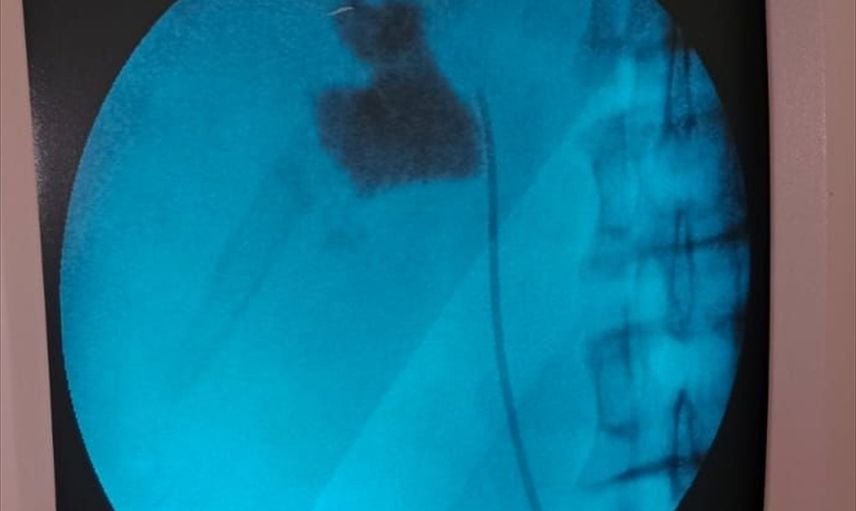

Kırşehir'de, Eğitim ve Araştırma Hastanesi'nde bir hastanın böbreğindeki 6 santimetrelik taş, kapalı ameliyat yöntemiyle alındı.

Hastaneye başvuran İlhami Çakır'ın yapılan kontrollerinde, sol böbreğinde 6 cm boyutunda bir taş tespit edildi. Üroloji Kliniği'nden Uzm. Dr. Talip Göktaş ve ekibi, kapalı böbrek taşı yöntemi PNL ile başarılı bir ameliyat gerçekleştirdi.

Ameliyat sonrası bir gün içinde taburcu olan Çakır, operasyon ekibine teşekkür etti. Uzm. Dr. Göktaş, hastaların bu yöntemle açık ameliyatlara göre daha hızlı bir iyileşme süreci yaşadığını belirterek, "Hastamız 1 gün sonra taburcu edildi. Bu yöntemle hastalarımız daha konforlu bir şekilde süreç atlatabiliyor. Son 5 yıl içinde hastanemizde 50'nin üzerinde bu tarz başarılı ameliyat gerçekleştirdik," ifadesini kullandı.